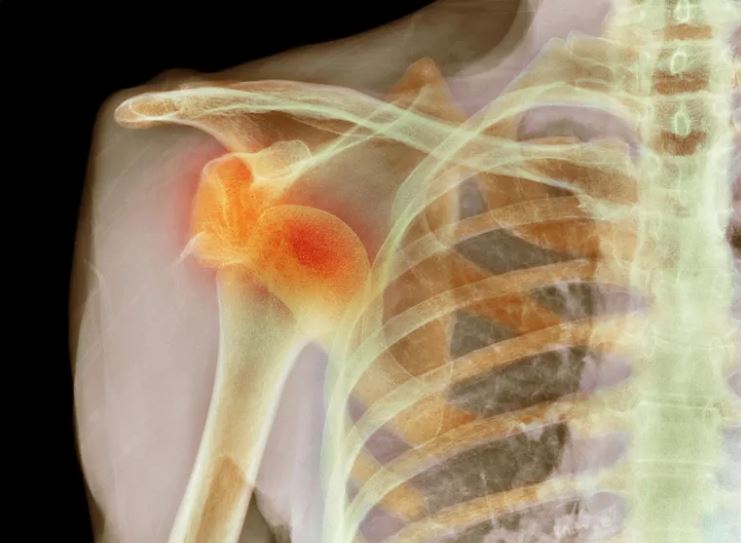

Rotator Cuff Partial Tear

The rotator cuff is an assemblage of tendons and muscles that surround the shoulder joint.

It is the tendon, part of the rotator cuff that may be damaged causing a rotator cuff tear.

When the rotator cuff tendon is torn, shoulder movements become painful and weak. Uneasiness can also appear with activity and even sleeping.

A partial tear of the rotator cuff is a damaged part of the rotator cuff tendons, where the tear does not interfere all through the tendons.

A Rotator cuff tear is called partial when the top part of the tendon is sometimes damaged, or when the bottom part of the tendon is damaged, or in some cases, the inner part of the tendon can be damaged.